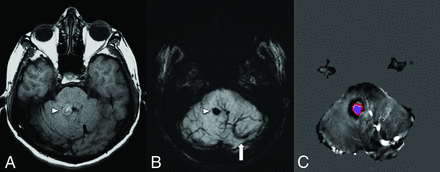

The triggered angiogenesis, which forms fragile vessels prone to hemorrhage as well as recurrent cycles of angiogenesis and microbleeds ultimately lead to the formation of CCMs.10 The following anatomic factors predispose to the development of CCMs within the drainage territory of a DVA: infratentorial DVA location, drainage of the collector into a deep vein, torsion of the draining vein, ≥5 medullary veins draining into a collector, stenosis of >55% of the medullary veins, and an acute angle between the medullary and the collector vein of ≤106.5°.8,11⇓-13 Note that most of the above-mentioned anatomic factors contribute to a decreased outflow of the DVA, thus supporting a venous congestion model of the formation of CCMs in the vicinity of a DVA. Systematic factors such as major infectious illness, chronic inflammatory disorders, and radiation exposure/treatment are also implicated in the formation of CCMs.12 The proinflammatory state is believed to promote thrombosis within the DVA, raising the venous pressure to promote an environment for CCM formation.12 Topographical location of CCMs are important as cortical or juxtacortical location or limbic involvement are more prone to seizure.14 Brainstem CCM may cause cranial neuropathy through the involvement of the cranial nerve nuclei, intra-axial cranial nerve pathway or even direct extension into the cisternal cranial nerves (Fig 2).15 Hemorrhagic propensity of CCM hemorrhage is based on the history of prior hemorrhage and this can be quantitatively analyzed through the CCM hemosiderin burden and its evolution over time on quantitative susceptibility mapping (QSM).16,17 Higher mean susceptibility value on QSM positively correlates with patient age and prior hemorrhagic episodes, whilst patients with clinically stable CCM demonstrate lower mean susceptibility value (Fig 3).16,17

A patient with right facial pain and dysesthesia. SWI (A) shows a posterior pontine DVA (arrow) and an associated CCM (arrowhead) involving the intra-axial and cisternal segments of the right trigeminal nerve. FLAIR (B) demonstrates hyperintense edema along the right lateral aspect of the pons (arrowhead). Coregistered T2 sampling perfection with application-optimized contrasts by using different flip angle evolutions (SPACE sequence; Siemens) (C) confirms CCM involvement of the right trigeminal nerve.

A middle-aged patient with new-onset ataxia. T1WI (A) and SWI MIP (B) show a CCM in the right superior cerebellar peduncle (arrowheads) and a large left cerebellar DVA with the collector vein (arrow) draining into the transverse sinus. Quantitative susceptibility mapping (C) analysis of the CCM shows a high mean susceptibility value of 858 parts per billion (with threshold). An ROI with a red boundary represents the exclusive object boundary, and the purple area represents thresholded pixels (150 parts per billion). SWIM (Siemens) parameters: TE = 20.00 ms; TR = 27.00 ms; flip angle = 150; resolution = 0.937 × 0.937 ×2.5 mm. Images courtesy of Dr E. Mark Haacke.